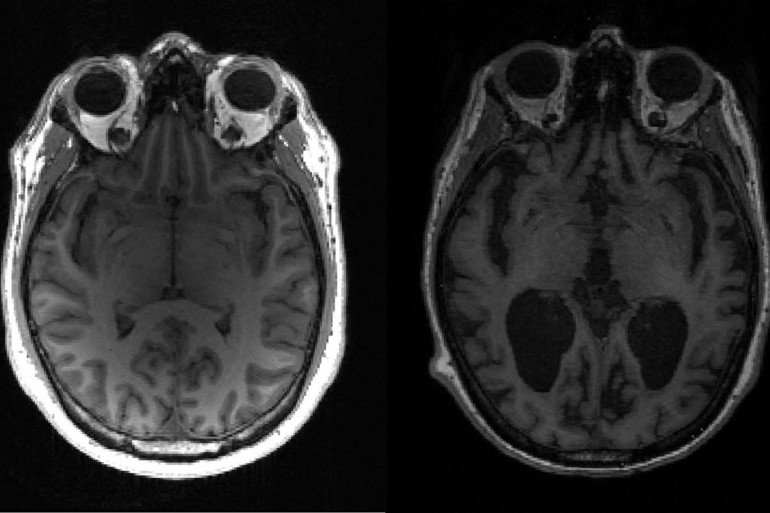

Une IRM d'un patient atteint de la maladie d'Alzheimer

Crédit : TIMOTHY RITTMAN / UNIVERSITY OF CAMBRIDGE / AFP